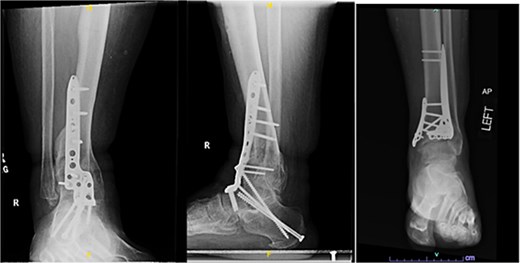

A 57-year-old male with a body mass index (BMI) of 48.7 kg/m2 and multiple comorbidities, including asthma, coronary artery disease, hypertension, hyperlipidemia, ischemic cardiomyopathy, obstructive sleep apnea, and hypothyroidism, following a motor vehicle collision when he lost control of his vehicle due to a coughing spell. His injuries included bilateral pilon fractures (Fig. 1), a T2 superior endplate fracture, and bilateral pulmonary contusions. He initially presented to a regional hospital and was transferred to our facility 10 days after the injury.

Anterior-to-posterior (AP) radiographs of patient 1 obtained 10 days after injury, upon transfer to our facility, demonstrating bilateral pilon fractures.